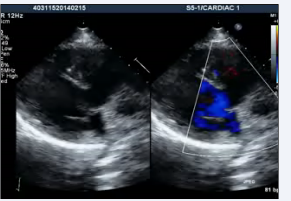

A 22-year-old male was referred to our tertiary care institute with a diagnosis of double outlet right ventricle with a ventricular septal defect and malposed great arteries. The patient was evaluated in the referring institute for atypical chest pain for ten days without any significant past history. A clinical examination, including cardiac testing, was normal, and the resting oxygen saturation was 98% on room air. Although the transthoracic echocardiographic window was poor, it revealed the patient had situs solitus, and there was AV and VA concordance. The aorta was located to the left and anterior to the pulmonary artery (Figures 1,2, video 1,2)

Figure 1: Transthoracic echocardiogram apical 4 chamber view showing AV and VA concordance

Figure 2: Transthoracic echocardiogram basal short axis view showing aorta to the left and anterior of pulmonary artery